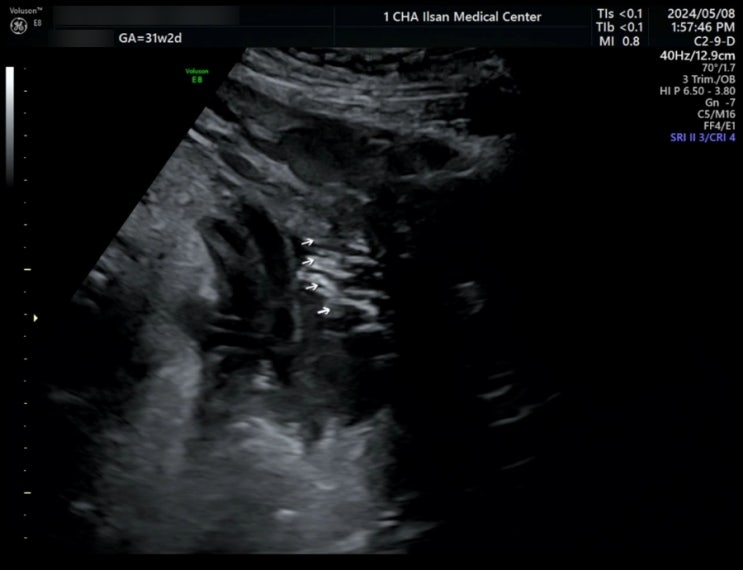

#52. 임신 31주 2일 일산차병원 정기검진, 초음파검사(머리카락이 난 아기), 백일해 주사 접종

분만병원 History 2024.03.05.(화) 10:00 산과 김의혁 교수님 초진 2024.04.02.(화) 임당검사, 입체초음파...